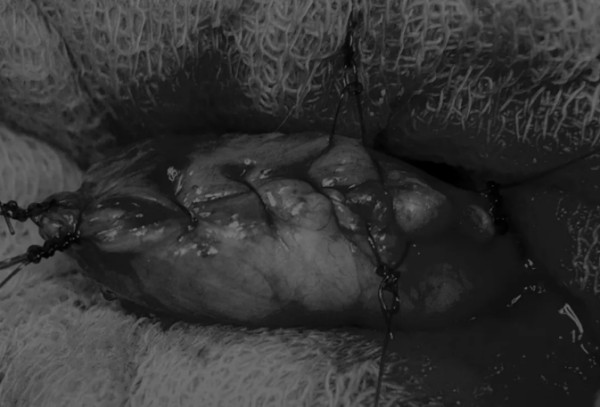

膀胱创面采用单丝合成可吸收缝线缝合,采用外科医生习惯的缝合方式,但注意不要刺穿黏膜层(图6、图7)。

图6 使用简单的连续缝合。尽量不要用针刺穿黏膜层(箭头),以免缝线与尿液接触

图7 缝线应带入足够的切口两侧的膀胱组织,以确保在膀胱充盈时,没有伤口裂开